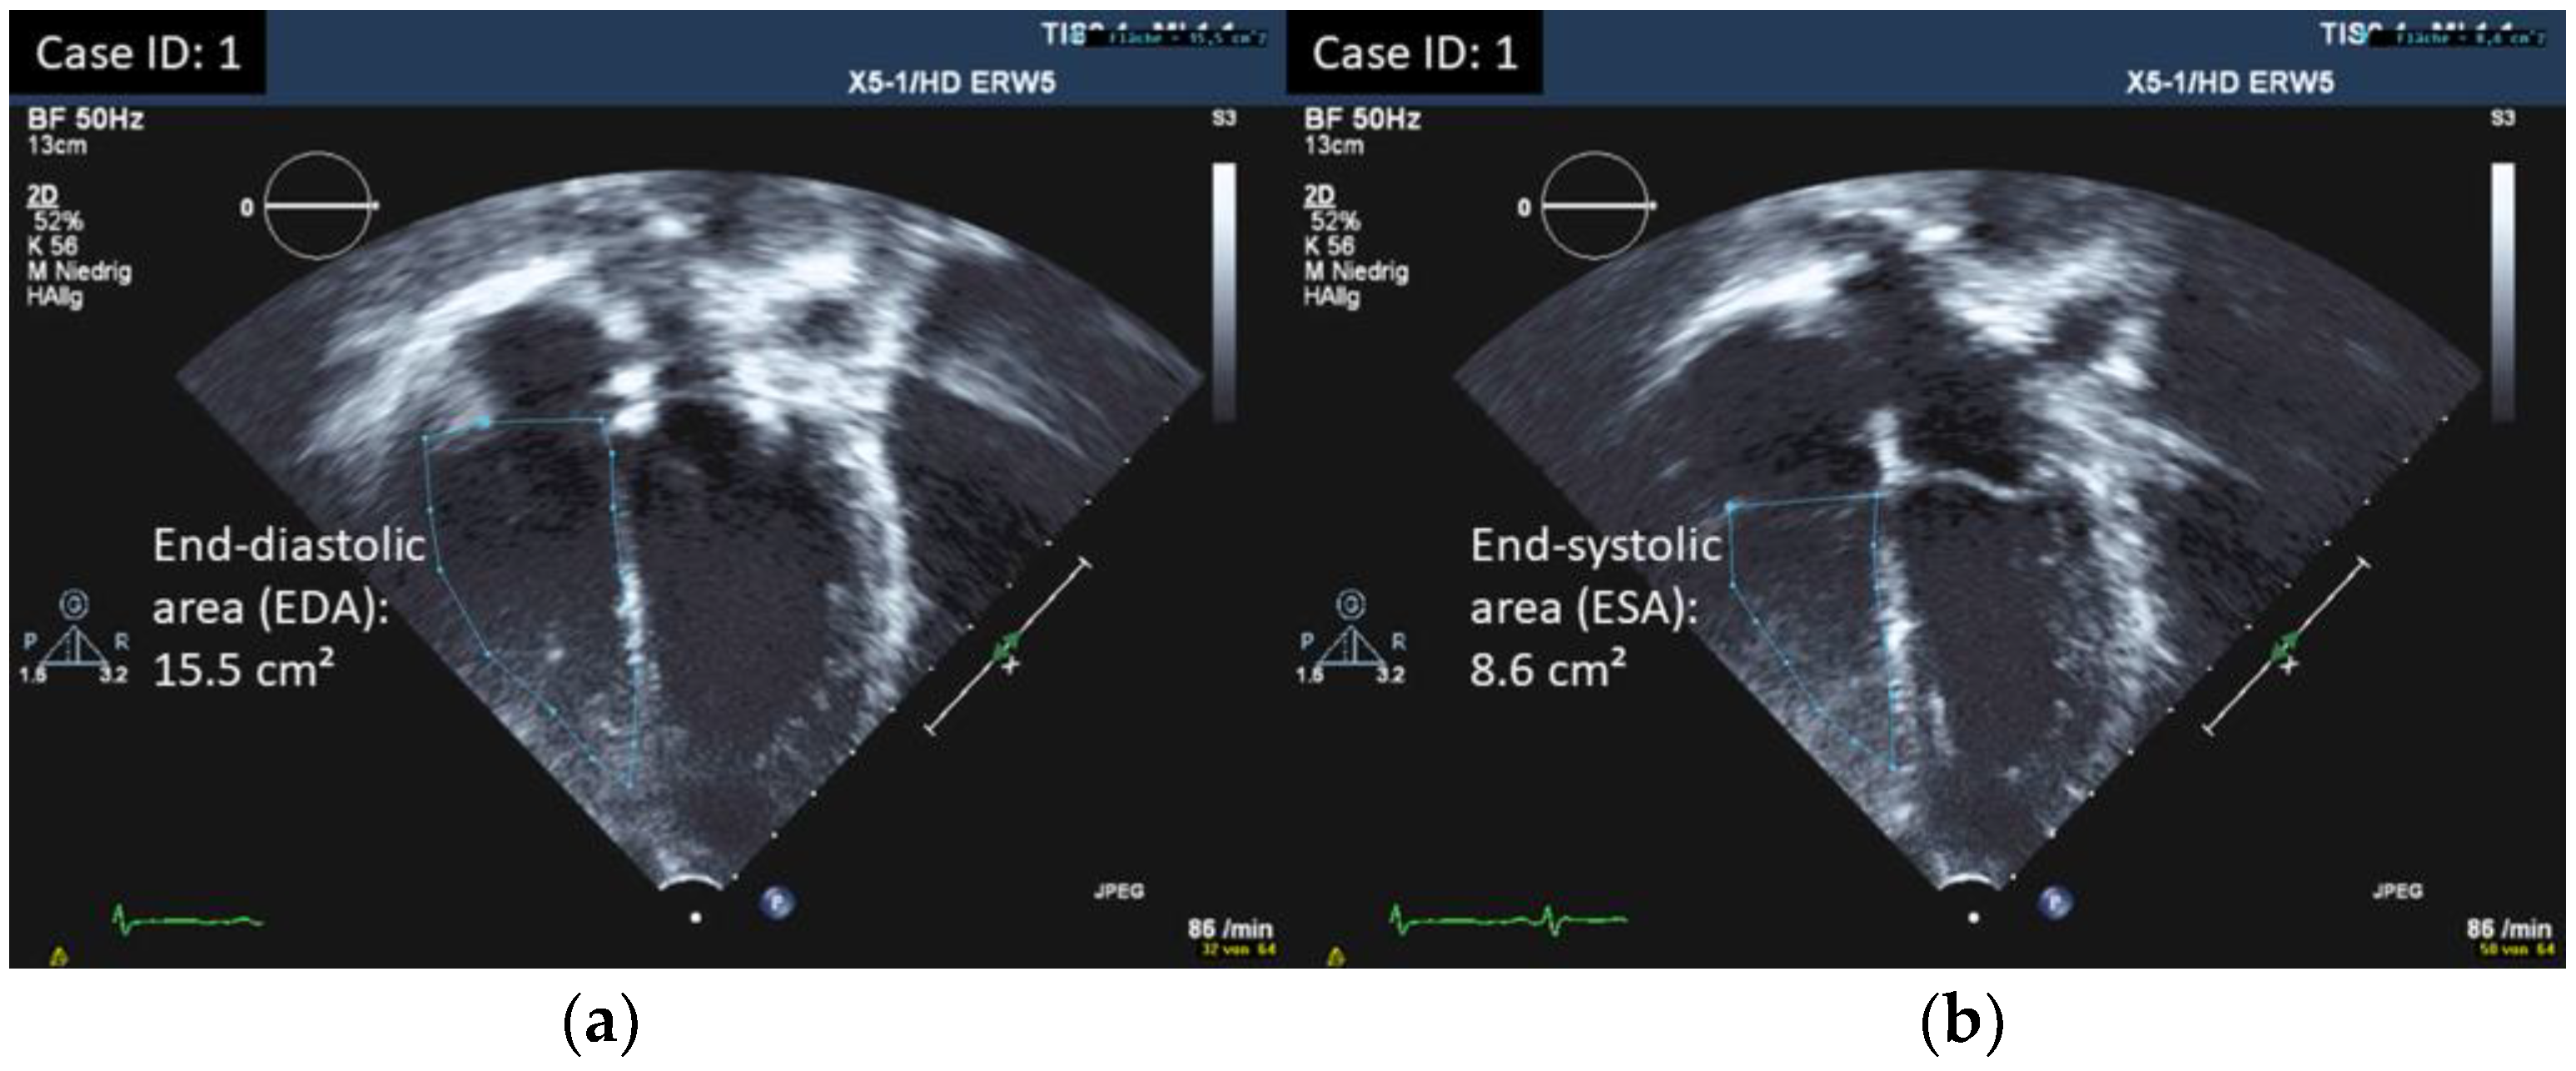

| (a) | |||||||

| ID | TAPSE cm | RV GLS % (ped.) | RV FWS % (adult) | TV S’ Vmaxcm/s | RV FAC % | RV-MPI | |

| 1 | 1.9 | −22.6 | / | 12.6 | 44.5 | 0.24 | |

| Parameter | n | Mean | SD | 25% | Median | 75% | Min | Max |

|---|---|---|---|---|---|---|---|---|

| TAPSE cm | 18 | 1.96 | 0.26 | 1.83 | 1.90 | 2.08 | 1.50 | 2.70 |

| TV S’ cm/s | 18 | 12.84 | 3.41 | 11.25 | 12.25 | 14.15 | 8.40 | 22.90 |

| RV-FAC % | 18 | 42.09 | 3.68 | 40.51 | 41.80 | 43.07 | 34.00 | 49.00 |

| RV-MPI | 18 | 0.28 | 0.07 | 0.23 | 0.28 | 0.33 | 0.21 | 0.43 |

| TV E/A | 18 | 1.36 | 0.29 | 1.22 | 1.38 | 1.56 | 0.70 | 1.80 |

| TV E/e’ | 18 | 5.04 | 1.51 | 3.75 | 5.00 | 5.78 | 3.00 | 8.82 |

| RV strain % | 18 | −22.72 | 3.17 | −23.98 | −22.78 | −22.31 | −28.00 | −15.10 |